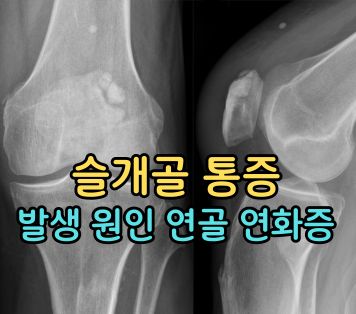

슬개골 통증 원인

슬개골 통증 원인은 슬개골 탈구 또는 슬개 대퇴 통증 증후군 때문일 가능성이 높습니다. 이런 질환이 나타나는 이유는 외상 또는 여성의 경우 평소 운동을 잘 하지 않다가 다이어트를 목적으로 운동을 시작한 경우 주로 발생하게 됩니다.

무릎의 중앙에 자리한 접히는 부분에 있는 뼈를 슬개골이라고 하는데 슬개골 탈구는 이 슬개골이 위치해야 할 자리를 이탈하는 것이며, 대퇴 통증 증후군도 비슷하게 슬개골과 대퇴골이 잘 맞물리지 않아서 발생하게 됩니다.